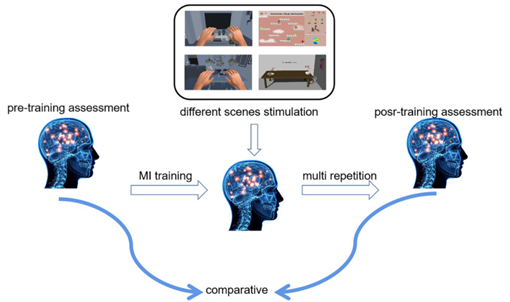

图4 对照实验设计图

在这项研究中,我们设计了一个对照实验,比较和分析大脑神经活动的变化,并使用不同虚拟场景的刺激来确定运动图像的识别率,以发现神经深度激活的机制。图4显示了实验的示意图。我们在训练前评估了受试者的运动想象能力,然后受试者进行了多重运动想象训练。完成培训后,参与者完成了培训后评估。